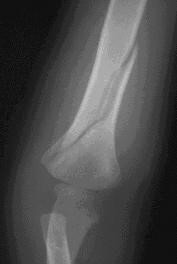

Image #4:

Spiral Fracture of the Humerus

(AbuseWatch.net, n.d.)

Seven-year-old Nick comes to the emergency room with an injured arm. His mother says he fell off the trampoline when he was jumping around and playing with his friend. An X-ray is ordered to assess for any breaks. When Nick’s arm is X-rayed, a spiral fracture of his humerus is identified.

Case Study 4

What indicators are present? Spiral fracture, the explanation for the injury is not plausible

Is there reasonable cause to suspect abuse or maltreatment? Yes

Is there a parent or other person responsible for the suspected abuse or maltreatment? Mother

What are your next steps? Call ChildLine.